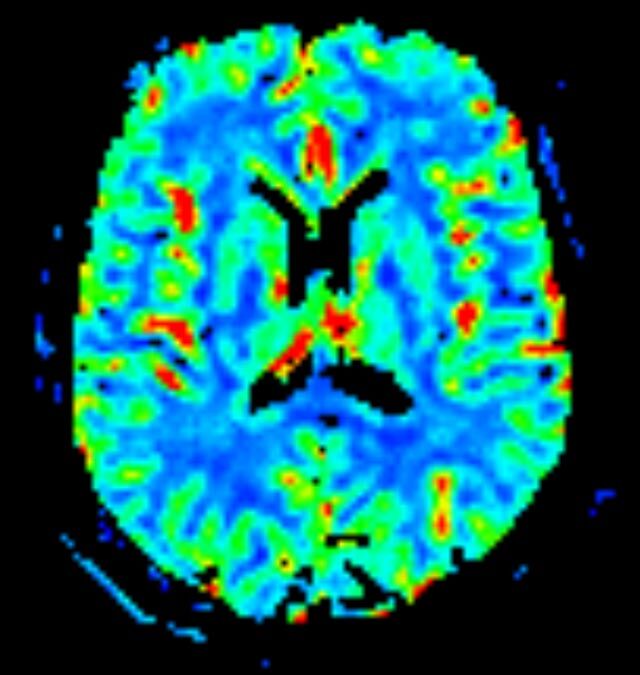

• Diffusionswichtung

• Perfusionswichtung

• Suszeptibilitätswichtung

• MR-Spektroskopie

Diese Verfahren werden bei verschiedenen Fragestellungen in verschiedenen Körperregionen in die Messprotokolle sinnvoll eingefügt. Teilweise können dadurch Differenzierungenverschiedener krankhafter Prozesse verbessert werden.